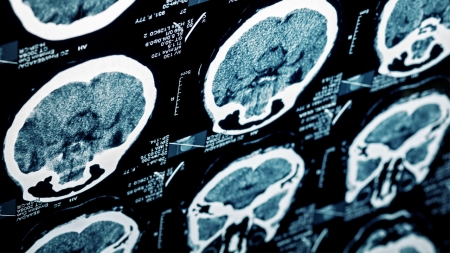

뇌졸중은 뇌에 피를 공급하는 혈관이 막히거나 터져 생기는 대표적인 뇌 질환입니다.